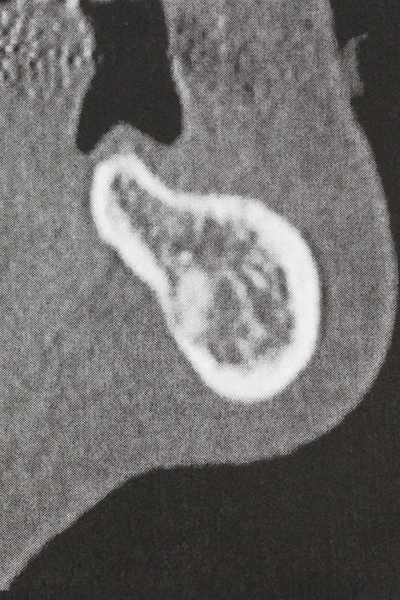

En la extracción de bloques óseos la piezocirugía también presenta ventajas adicionales: Además de la alta precisión en la osteotomía que ya se ha descrito antes, se ha comprobado que el uso de los delgados insertos de sierra resulta especialmente cuidadosas con el hueso. Frente a esto, sobre todo cuando se usan las fresas de Lindemann, cabe esperar pérdidas en la extracción significativamente más altas debido al mayor grosor de la parte frontal del cabezal (Lakshmiganthan, Gokulanathan et al. 2012). La separación basal que se necesita en particular en los injertos de bloque extraídos de forma retromolar se ve facilitada mediante sierras perpendiculares especialmente previstas a tal fin, lo que permite considerar que la cirugía piezoeléctrica es un procedimiento preciso y seguro para la obtención de bloques de hueso en el área retromolar (Happe 2007) (fig. 1-12).